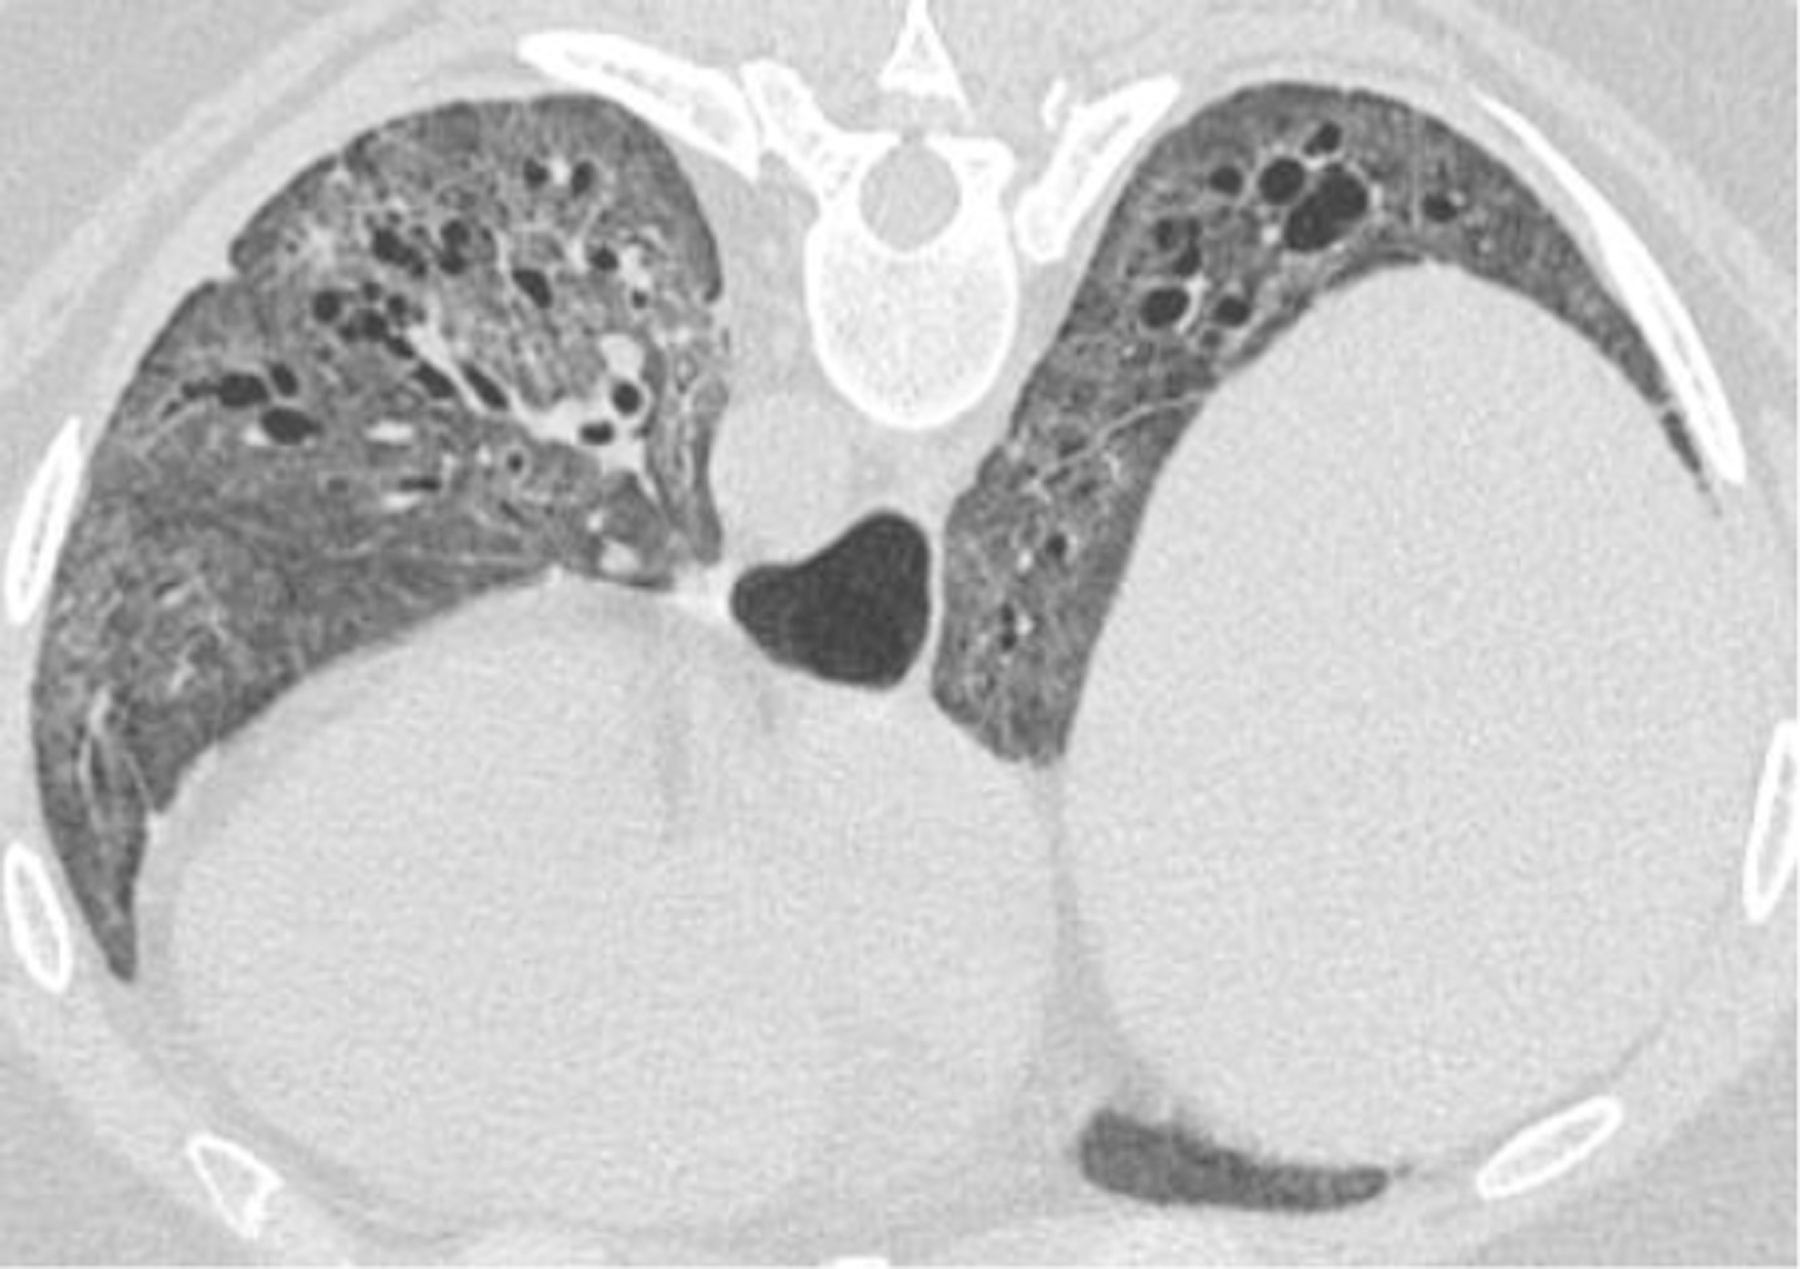

Figure 2.

69-year-old female with CREST syndrome (Calcinosis, Raynaud’s phenomenon, Esophageal dysmotility, Sclerodactyly, and Telangiectasia) and known interstitial lung disease. Usual Interstitial Pneumonia pattern noted.

2B. Exuberant honeycombing in the lower lobes (exuberant honeycombing sign).